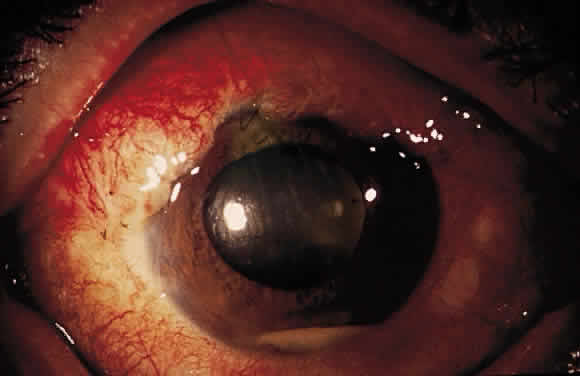

HYPHEMA

Hyphema is a common postoperative occurrence in glaucomatous eyes after filtration surgery, surgical peripheral iridectomy, and trabeculotomy. Bleeding commonly arises from the ciliary body or cut ends of the Schlemm's canal, although it also might arise from the corneoscleral incision or iris.

In general, hyphema presents at surgery or within the first 2 or 3 days after surgery. Intraoperatively, if a bleeding spot does not stop spontaneously, it must be identified and coagulated. During filtration surgery, bleeding is decreased by performing the internal sclerostomy as far anteriorly as possible.

In most cases, no treatment is necessary and the blood is absorbed within a brief period of time. Cycloplegics, corticosteroids, restriction of activity, and elevation of head of the bed 30° to 45° (to prevent blood from obstructing a superior sclerostomy) are recommended. Increased IOP can occur, particularly if the filtering site is obstructed by a blood clot, and it should be treated if necessary with aqueous suppressants. Injection of tissue-plasminogen activator may be considered (see later). Surgical evacuation is considered depending on the level of IOP, size of hyphema, severity of optic nerve damage, likelihood of corneal blood staining, and presence of sickle trait or sickle cell anemia (infarction of the optic nerve can occur at relatively low IOP, and carbonic anhydrase inhibitors are contraindicated). Liquid blood can be easily removed with irrigation. If a clot has formed, it can be removed by expression with viscoelastic or with a vitrectomy instrument set at low vacuum.